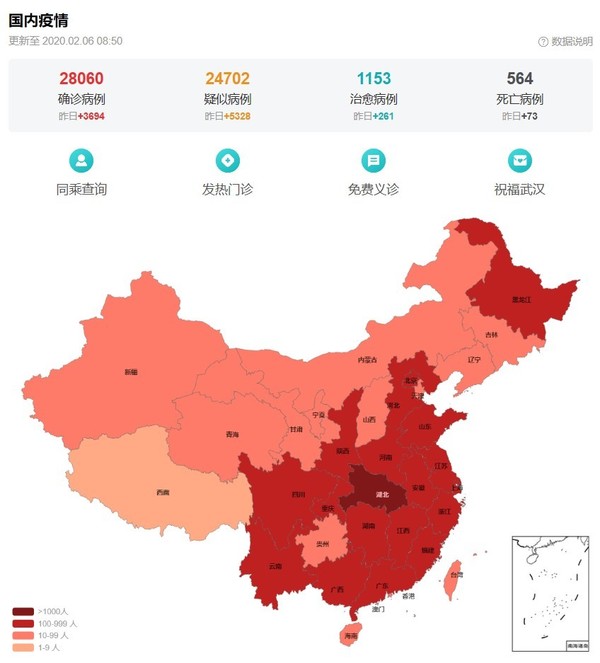

截止發稿前,新型冠狀病毒肺炎國內疫情確診病例28060例,疑似病例24702例,治愈病例1153例,死亡病例564例。國家衛健委專家組成員、北京地壇醫院感染二科主任醫師蔣榮猛在接受采訪時表示:“從1月23號開始算,到6號是第一個潛伏期,再往后算14天,可能是2月20號。從目前的情況來看,疑似病人在增加。在下一個階段,有可能有更多的疑似病人會進入到我們的視野中進行排查。”

新型冠狀病毒疫情動態